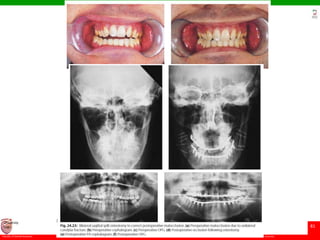

Bilateral condylar malunion

• results in anterior open bite and class II jaw relationship.

• The correction is achieved by adjusting the maxilla to

accommodate this reduced posterior face height by carrying

out a posterior maxillary impaction.

• This results in an increase of the occlusal plane angle, but

this is of little significance and will result in a stable

correction of the anterior open bite component of the

deformity, as a consequence of mandibular autorotation.